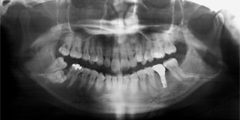

写真(2)

骨が再生されインプラントときちんとくっついている状態の写真です。